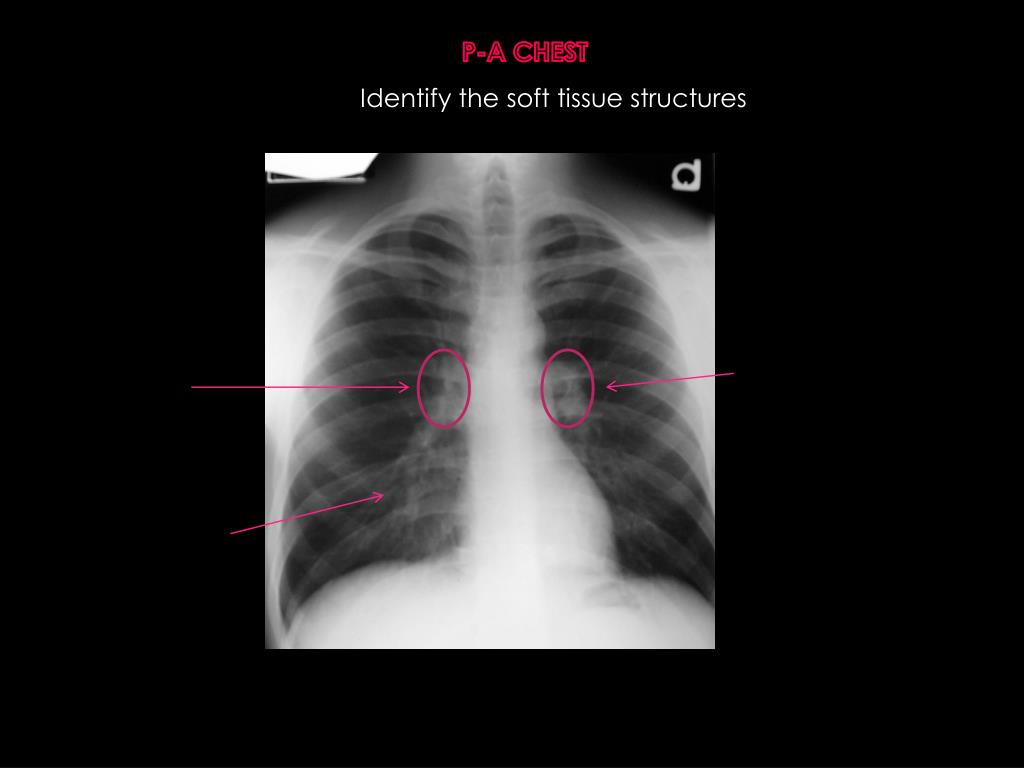

9. P-A CHEST Identify the soft tissue structures

10. P-A CHEST Identify the soft tissue structures left hilum RightHilum Pulmonary vessels (bronchovasicular markings)